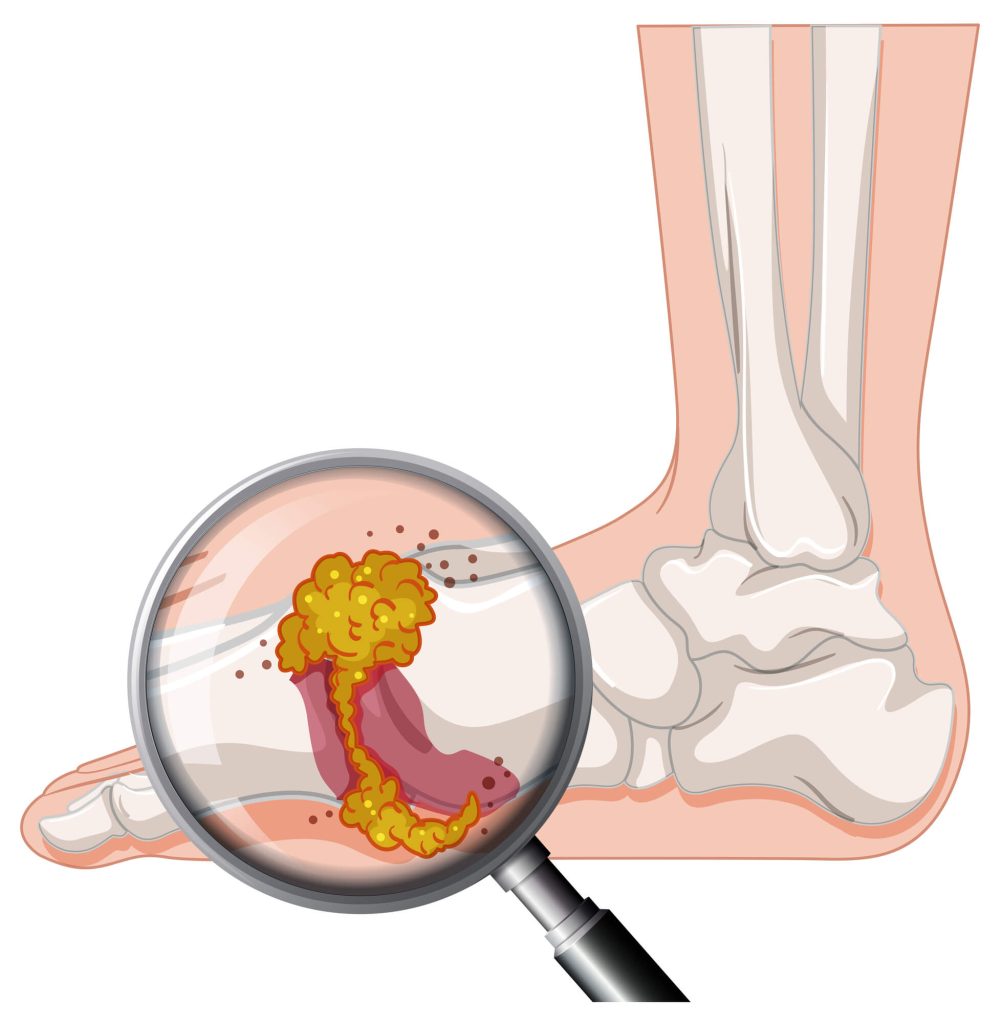

통풍은 몸속에 요산이 여러 이유로 배출되지 못하여 과다하게 쌓여 발생하는 염증성 관절 질환으로, 일반적으로 관절에 강한 통증과 부기를 유발합니다. 요산은 프린 과다 섭취, 신장 기능 저하 등으로 축적되며, 이는 주로 엄지발가락의 관절에서 가장 흔하게 나타납니다. 통풍 발작은 갑작스럽고 극심한 통증을 동반하여, 일상생활에 큰 지장을 줄 수 있습니다. 또한, 통풍은 재발할 위험이 높고, 만성질환으로 발전할 수 있으므로 조기 진단과 치료가 중요합니다.

통풍은 요산 수치의 상승으로 인해 발생하며, 여러 가지 원인이 존재합니다. 육류, 해산물, 알코올, 설탕이 많이 포함된 음식 및 음료를 과도하게 섭취하는 것, 비만, 유전적 소인, 신장 질환 등이 주요 원인입니다. 통풍 증상으로는 발작적인 심한 통증, 종아리의 부기 및 발열이 동반된 관절의 통증이 있으며, 대개는 밤이나 이른 아침에 발생합니다. 이러한 증상은 수일간 지속될 수 있으며, 치료하지 않으면 재발 빈도가 증가할 수 있습니다.

통풍 진단은 다양한 검사 방법이 사용됩니다. 임상적으로 가장 중요한 것은 혈액 검사를 통해 혈중 요산 수치를 확인하는 것입니다. 요산 수치가 6.8mg/dL 이상인 경우 통풍으로 의심하게 됩니다. 또한, 관절에서 체액을 채취하여 요산 결정체의 존재 여부를 확인하는 관절천자도 시행될 수 있습니다. X-ray와 MRI와 같은 영상 검사는 관절 손상의 정도를 평가하는 데 도움을 줄 수 있습니다. 정확한 진단을 위해 의료 전문의와 상담하는 것이 중요합니다.